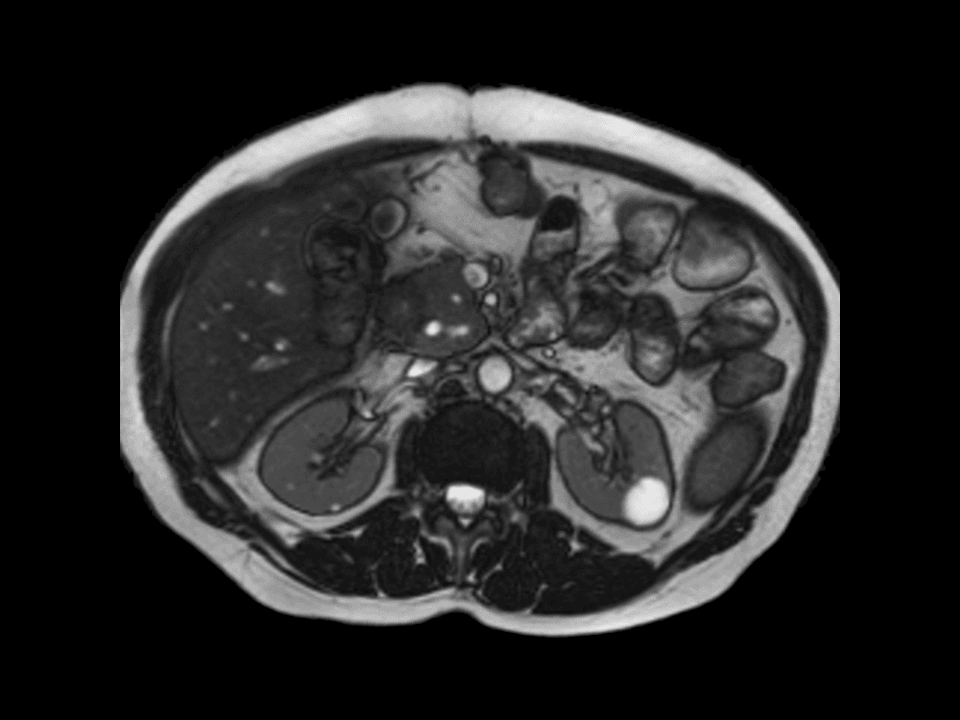

The combination of Body Matrix and IsoCenter Matrix is an ideal combination for an easy patient setup and state-of-the-art imaging performance.